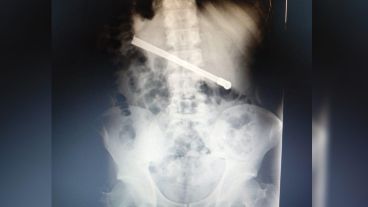

Al continuar con el malestar, le realizaron una placa radiográfica en la Unidad Penitenciaria ubicada en 27 de febrero al 7800, y pudieron determinar que había ingerido una bombilla de mate que quedó alojada transversalmente en la cavidad torácica.

En virtud de esto, el interno fue derivado al hospital Eva Perón para recibir una mejor atención, por lo que quedó internado para ser intervenido quirúrgicamente.